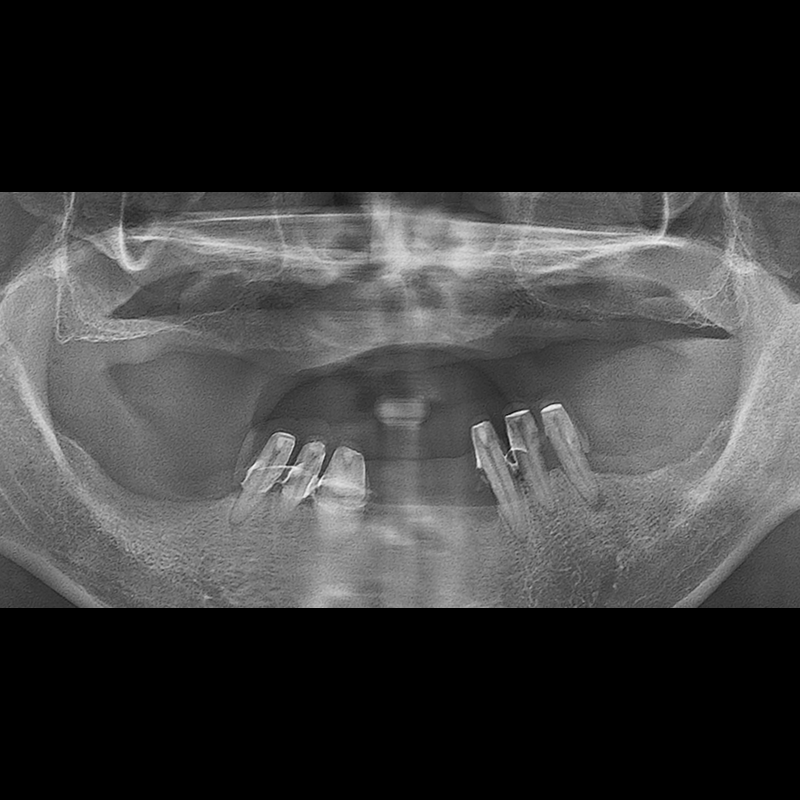

BEFORE AFTER

インプラント手術事例 2025.05.30

欠損した歯の部分と、生かしにくい歯の位置にインプラントを植立しました。